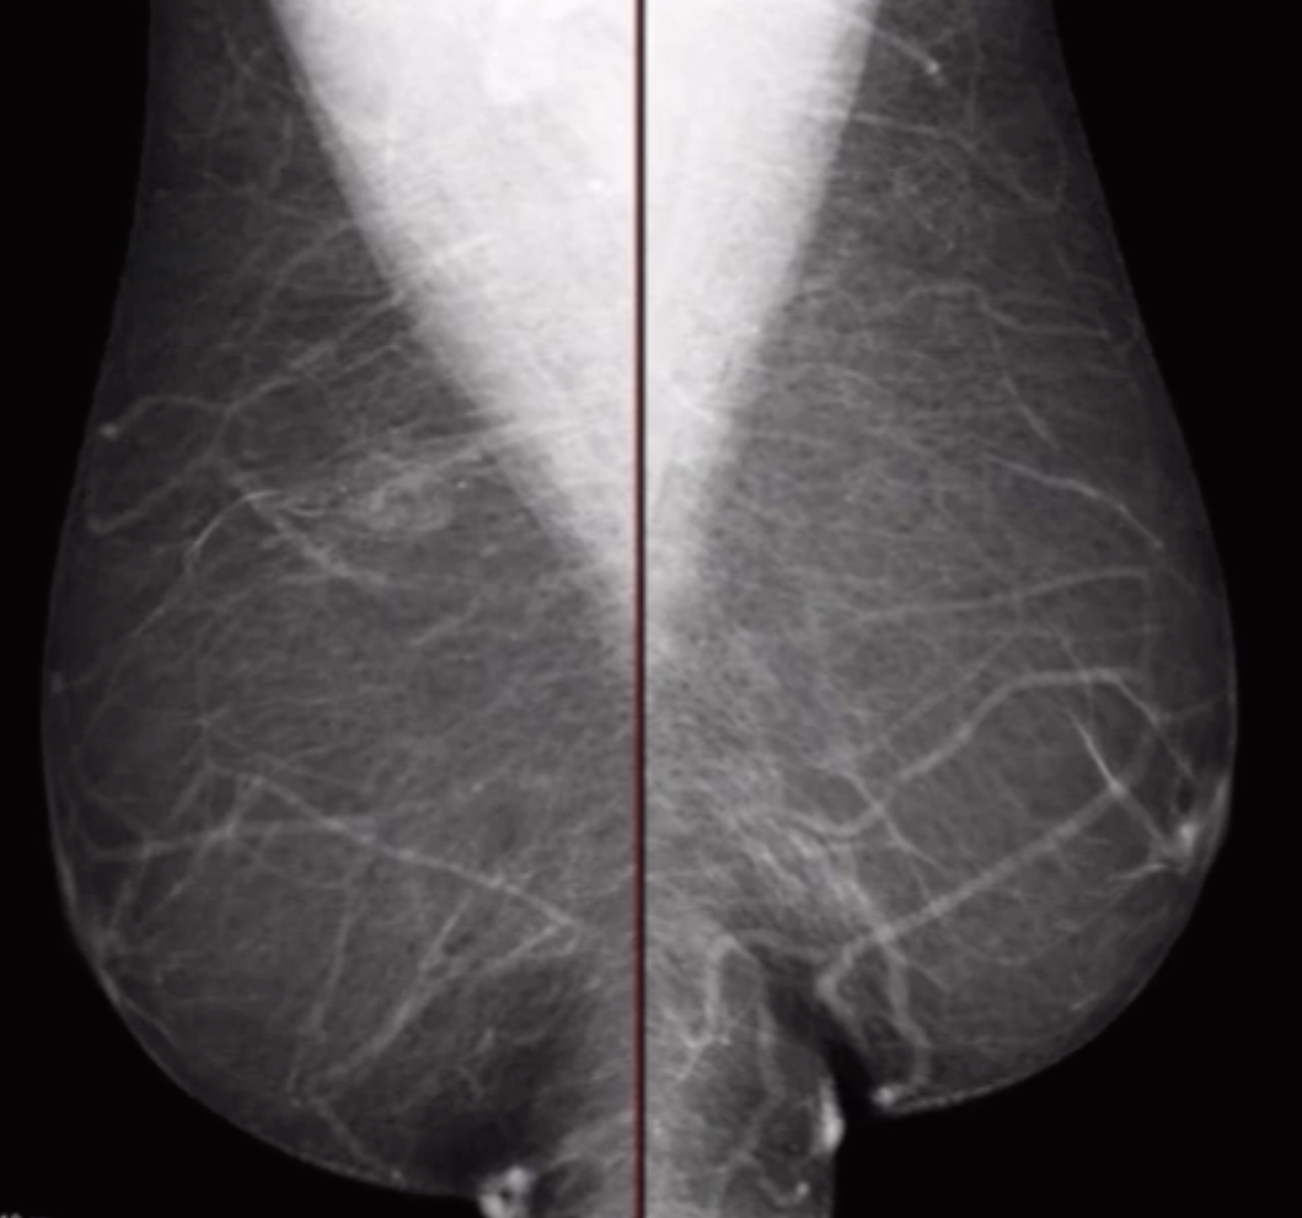

Pseudogynecomastia (Bitch tits)

• Basically boobs because you are fat and have fat deposition in your boob area but no actual breast tissue

• No focal palpable mass